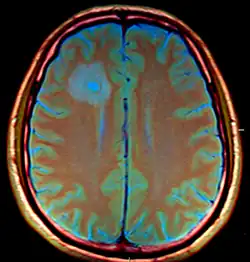

The CT images for the abscesses caused by Entamoeba histolytica are completely indistinguishable from the abscesses caused by any other organisms or causative agents. However, the brain abscesses are often observed in the frontal lobe or the basal ganglial regions.[1]

In addition, the CT results are often inconclusive and even the parasitologic stool examinations and abdominal ultrasonography often yield normal results. However, direct examination of the abscess capsule may exhibit necrotic material, foamy histiocytes, rare eosinophills and ingested erythrocytes.[1] Spheric structures may insinuate the presence of Entamoeba histolytica trophozoites with Masson's trichrome stain. Additionally, PCR based analysis of the CSF can be used to positively identify the parasite in the system .[6]